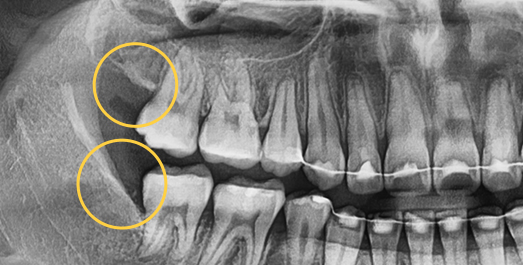

Extraction technique with nerve considerations

Using 3D CT, we evaluate the shape of the wisdom tooth, its roots, and surrounding nerves to support a safer extraction process.

Even advanced cases

can be extracted.

With extensive experience in numerous advanced cases and a wide range of wisdom tooth extractions, you no longer need to go to a university hospital.